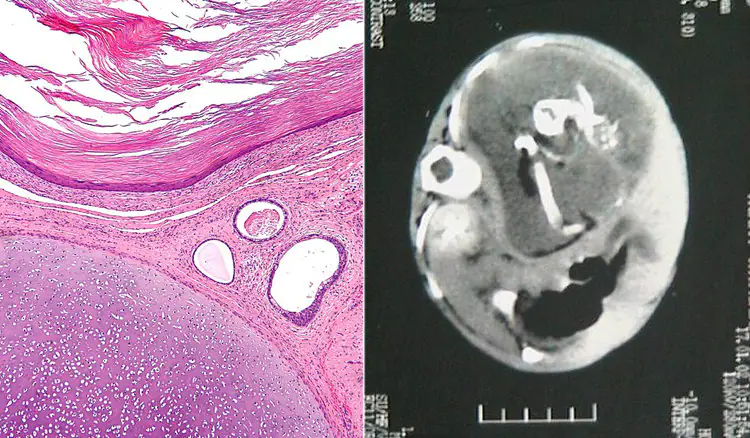

2 Tumors can have hair, teeth, bone, and even complex organs such as eyes and brain matter. In rare cases, they can also contain structures resembling a fetus.

Teratoma and Fetus in Fetu

Image Source: wikipedia, Nisreen M Khalifa et al

Named after the Greek words for “monster” and “tumor”, teratomas are tumors that result from abnormal development of germ cells and embryonic stem cells. Both these types of cells are pluripotent, that is, they are a type of stem cell that can develop into several types of tissues including those of intestines, lungs, nervous system, bones, teeth, and the tissues of various organs.

Tumors of these cells often result in the development of abnormal structures having even skin and cysts which may have abundant hair. Rarely, they could also develop into a malformed fetus which may even have a few complete body parts.

Teratomas develop in people of all ages and typically form in the ovaries, testis, or tailbone. They usually are harmless, unless they grow quite large, divert blood flow from vital organs, or result in autoimmune illnesses. Over a quarter of ovarian tumors and almost half of testicular cancers are teratomas. (source)